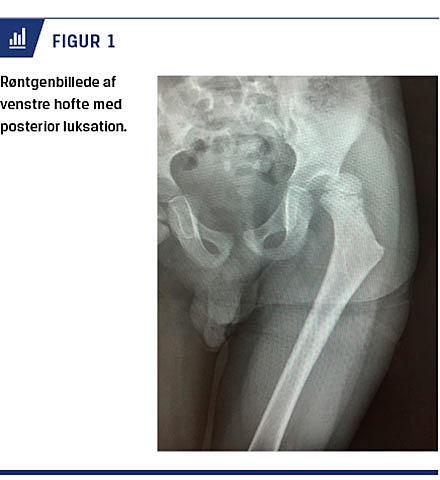

Med 12 dages mellemrum kom en fireårig dreng og en otteårig pige i akutmodtagelsen med venstresidige hoftesmerter efter fald under kælketure. Røntgen af begges hofter viste posterior luksation (Figur 1), hvorefter hofterne blev lukket reponeret i generel anæstesi. Dagen efter viste CT, at hofterne var på plads, og der var ingen tegn på ossøs ledskade. Patienterne blev begge udskrevet i velbefindende få dage efter.